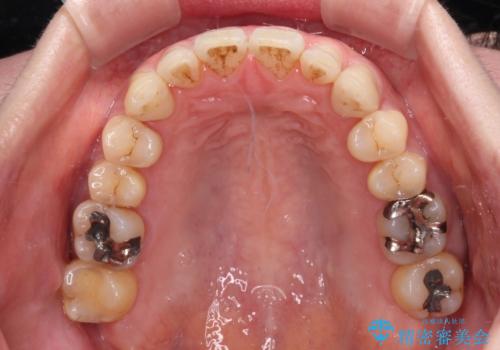

八重歯のインビザライン矯正治療

- 下顎の八重歯と、上下のクロスバイトを気にして来院された患者様です。

インビザラインを用い、下顎全体の後方移動、IPR(歯と歯の間を削る)と歯列全体を拡大させることで、歯並びを整えていくこととしました。

奥に位置していた上の前歯が下の前歯を乗り越える際、奥歯でものを咬むことができず、辛い時期が続きました。